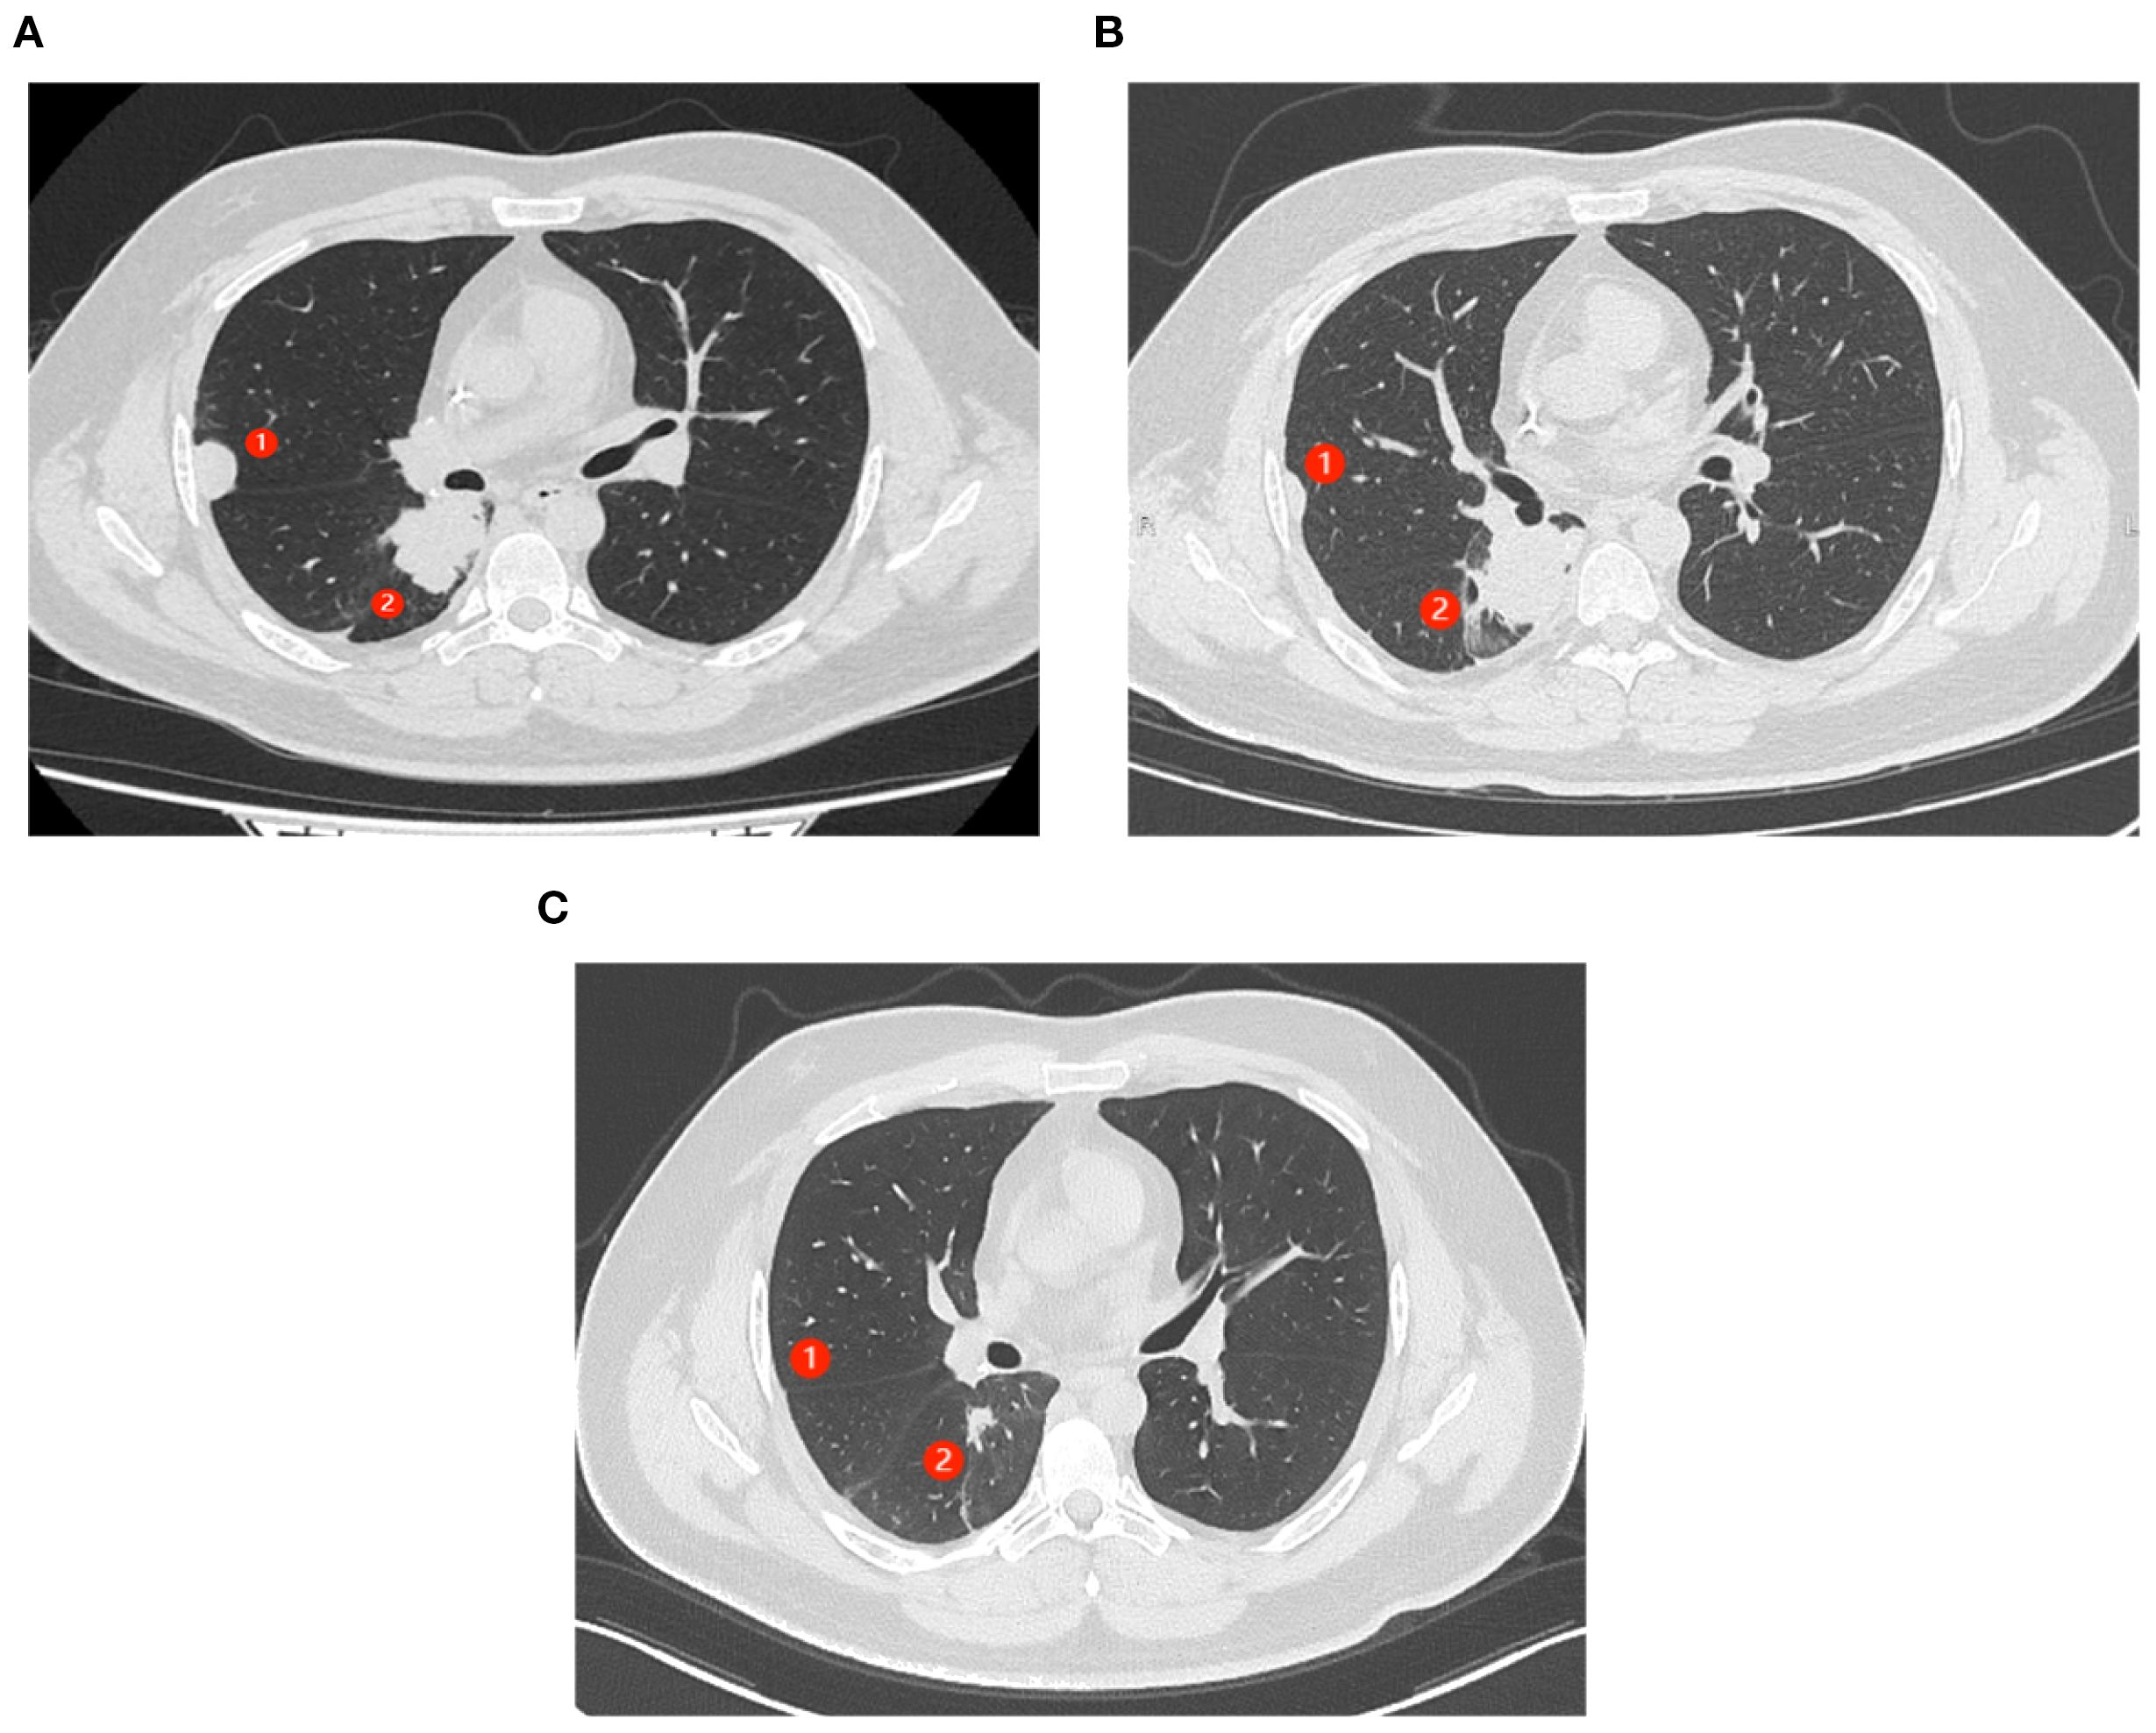

After resistance to the PD-1 inhibitor developed, genetic testing of peripheral blood and tumor tissue identified a vrafmurine sarcoma viral oncegene homolog B (BRAF) mutation in exon 15. Based on this finding, in August 2021, the patient commenced treatment with dabrafenib and trametinib. Computed tomography (CT) assessment indicated stable disease (SD), and his cough improved. Nine months later, he reported worsening cough and persistent right-sided chest pain. CT revealed a 2-cm pleural lesion (Figure 2A). The patient stopped BRAF-targeted therapy and was rechallenged with camrelizumab (200 mg, every 21 days) and apatinib (250 mg, once daily). Three months later, the pulmonary lesions remained stable. He then underwent RFA of the largest lesion in the hilar region of the right lung. The longest diameter of the target lesion was approximately 4.39 cm. Only partial ablation was achieved, as the current criterion for complete RFA applies to lesions 3 cm or smaller. Three months post-RFA, CT evaluation confirmed a PR in another pleural lesion that had not undergone RFA (Figure 2B). The patient continued combined treatment, and at 12 months post-RFA, CT evaluation demonstrated complete response of the pleural lesion and regression of the hilar lesion that had undergone RFA (Figure 2C). His chest pain resolved, and his cough diminished. Serial follow-up documented a sustained partial response. Camrelizumab was discontinued in July 2025, and the patient is currently maintained on oral apatinib therapy (250 mg once daily). Treatment-related toxicities have remained generally tolerable (Table 1).

Figure 2. Abscopal response in a patient with nephroblastoma following radiofrequency ablation (RFA). ① represents the lesion near the chest wall that did not undergo RFA. ② represents the lesion in the hilar region where RFA had been performed. (A) CT scans of the patient’s chest show progressing lung lesions before the initiation of RFA. (B) CT scan shows the resolution of ① after 3 months of therapy (C). (C) CT scans (axial views) show complete response (CR) of ① and partial response (PR) of ② after 12 months of therapy.